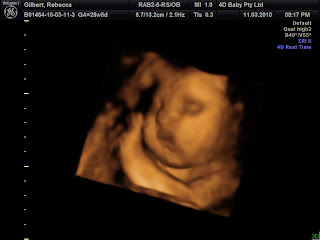

Here is my little boy at 28 weeks. Technology is getting so much better. My husband was showing a photo of this at work and someone asked him how old he was thinking the photo was of our new born and not done through ultrasound.

Enjoy!!